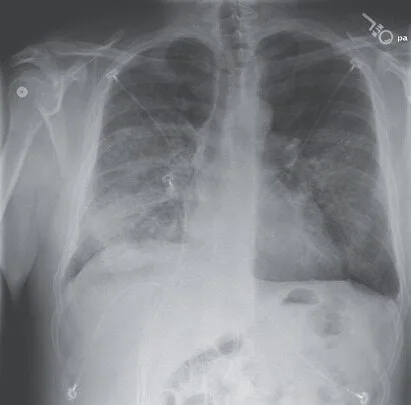

血肌酐水平下降至0.7mg/dL(62υmol/L),总胆红素水平下降至0.7mg/dL(12υmol/L),白蛋白为2.2g/dL,其他生化检查和肝功能均正常。白细胞计数为21600/mm3,未行白细胞分类计数。红细胞压积为35%,血小板计数为381000/mm3。胸片提示:双侧肺部浸润影进一步扩大(图1C)。

图1C. 患者住院第8天胸片显示两肺浸润影进一步加重。